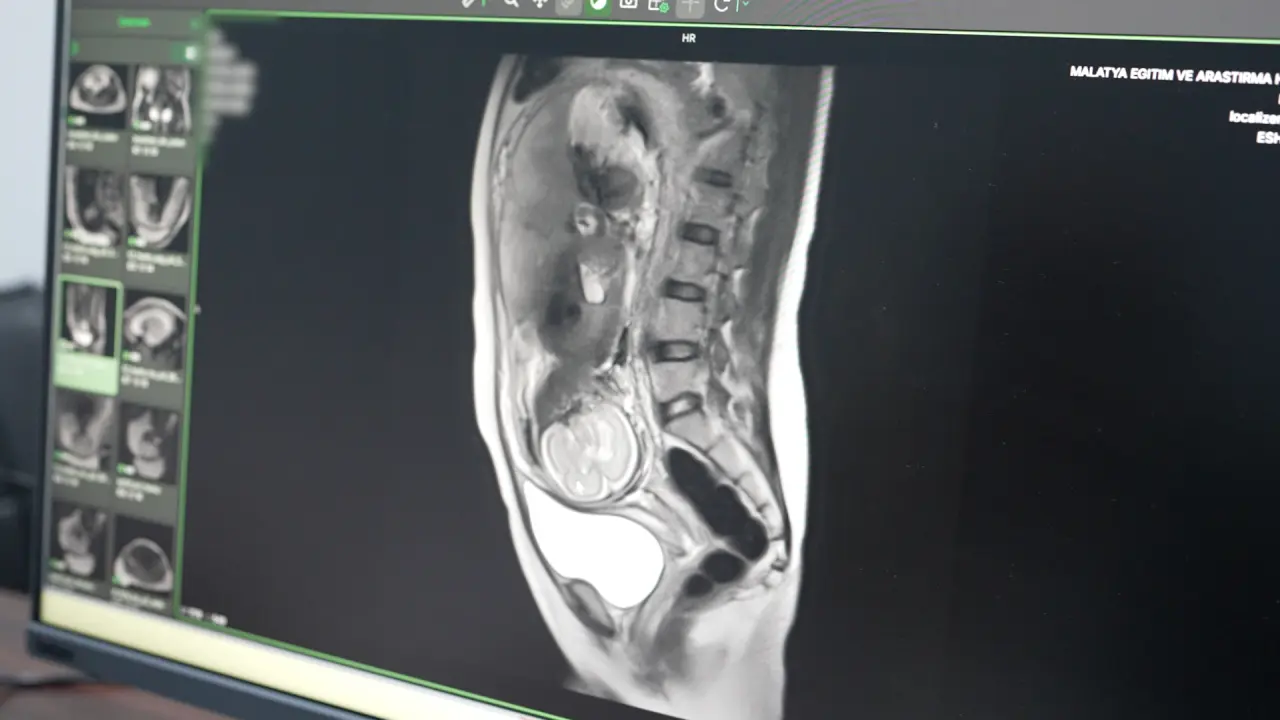

- Fetal MR: Anne karnındaki bebeklerin gelişim bozuklukları ve doğumsal anomalileri doğum öncesinde detaylıca tespit edilebiliyor.